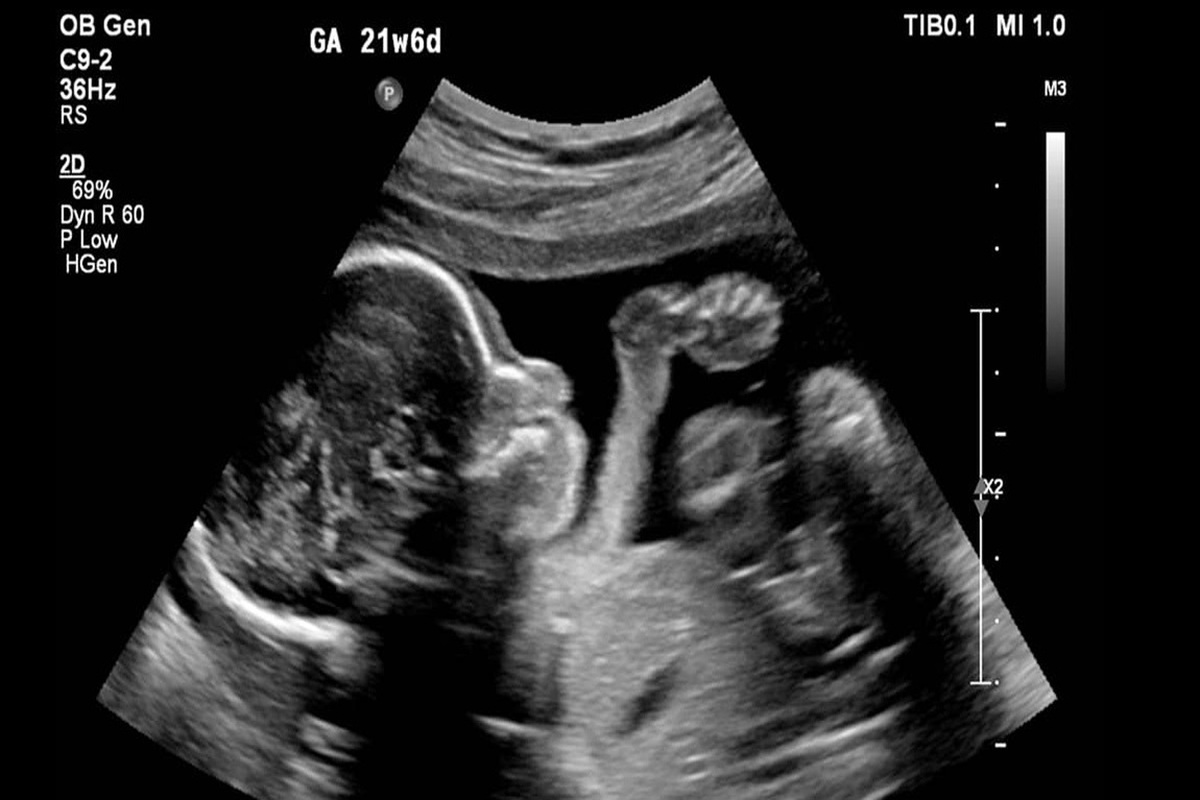

معاون درمان وزارت بهداشت با اشاره به راه‌اندازی و ابلاغ سامانه ملی باروری سالم، گفت: بیش از ۱۰۰ پرونده در زمینه سقط غیر قانونی، به مراجع قضایی ارسال شده و امیدواریم برخوردهای جدی و بازدارنده با این پرونده‌ها انجام شود.

وی درباره راه‌اندازی سامانه ملی باروری سالم، گفت: سامانه ملی باروری سالم ابلاغ شد. قرار است در قالب این سامانه از زمانی که تست حاملگی خانمی مثبت می‌شود و جنینی تشکیل می‌شود تا زمانیکه متولد می‌شود، در این سامانه ثبت می‌شود. به تدریج آزمایشگاه‌ها، پزشکان متخصصی و ... به این سامانه وصل می‌شوند و اگر احیانا نیاز به غربالگری باشد، در این سامانه ثبت می‌شود و اگر نیاز به سقط درمانی باشد، در این سامانه ثبت می‌شود تا بتوانیم یک جنینی را که تشکیل می‌شود تا زمان تولدش ردیابی کنیم تا این جنین‌ها از دست نروند و بتوانند به جمعیت سالم کشور اضافه شوند.